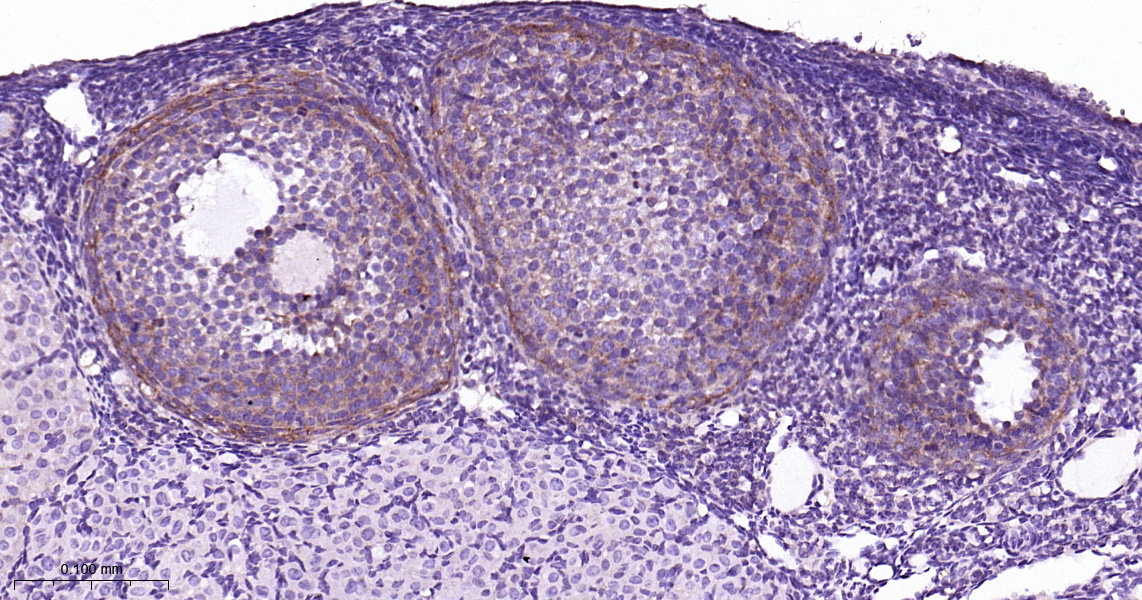

• IHC-P

IHC-P IHC-P1:50-200